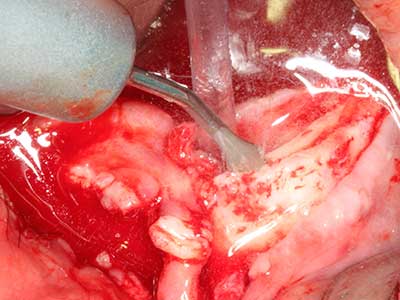

En la extracción de bloques óseos la piezocirugía también presenta ventajas adicionales: Además de la alta precisión en la osteotomía que ya se ha descrito antes, se ha comprobado que el uso de los delgados insertos de sierra resulta especialmente cuidadosas con el hueso. Frente a esto, sobre todo cuando se usan las fresas de Lindemann, cabe esperar pérdidas en la extracción significativamente más altas debido al mayor grosor de la parte frontal del cabezal (Lakshmiganthan, Gokulanathan et al. 2012). La separación basal que se necesita en particular en los injertos de bloque extraídos de forma retromolar se ve facilitada mediante sierras perpendiculares especialmente previstas a tal fin, lo que permite considerar que la cirugía piezoeléctrica es un procedimiento preciso y seguro para la obtención de bloques de hueso en el área retromolar (Happe 2007) (fig. 1-12).